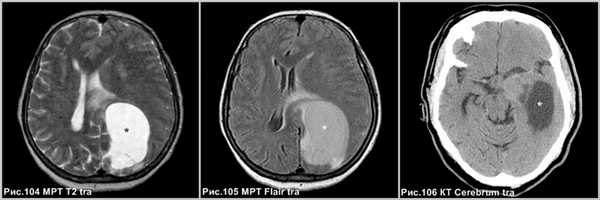

Крупная опухолевая киста, расположенная в теменно-затылочной области левого полушария большого мозга изоинтенсивная ликвору по Т2 и имеющая повышенный МР-сигнал по Flair (звёздочки на рис.104, 105), не сопровождающаяся перифокальным отёком. Кистозная опухоль левой височной доли, незначительно гиперденсна относительно ликвора (звёздочка на рис.106).

Поверхностная часть опухоли обычно простирается в субарахноидальное пространство. Ангиография показывает, что эти опухоли гиперваскуляризированны и получают кровоснабжение от менингеальных артерий. Характеристики МР-сигнала: →T1 и↑Т2 по отношению к серому веществу. Визуализационные особенности: отсутствие перитуморального отека и атрофия смежных поверхностей свода черепа [48].